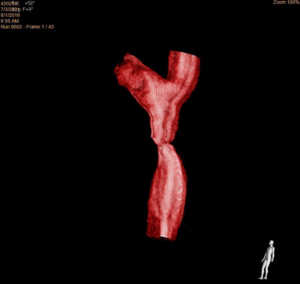

Zwężenie cieśni aorty u 15-letniej dziewczynki; A – aortografia, B – rekonstrukcja trójwymiarowa na podstawie aortografii rotacyjnej, C ? stan po implantacji stentu w miejscu zwężenia cieśni aorty.